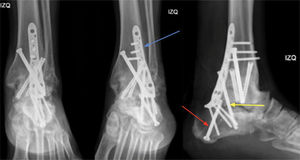

Proyecciones anteroposterior, mortaja y lateral de tobillo izquierdo. Resultados post op cirugía de revisión. Se aprecia aumento de la rigidez de constructo mediante una placa posterior tibiocalcánea (flecha azul), tornillo compresión interfragmentario a través de la placa (flecha amarilla)+tornillo calcáneo talar retrógrado (flecha roja).

El paciente presenta evolución clínica postoperatoria favorable, sin dolor, con heridas sanas y sin signos de infección o trombosis venosa profunda. Cultivos intraoperatorios de foco de no unión fueron negativos. Durante el último control médico (3 meses postoperatorios) paciente se encuentra sin dolor, tobillo fijo en 90° con buena alineación del retropié, marcha sin bastones, realizando kinesioterapia motora y reeducación de la marcha (figura 4). En su último control radiográfico se observaron elementos de osteosíntesis en posición adecuada y adecuada alineación del retropié, junto a signos de consolidación parcial con incipientes puentes óseos (figura 5). El paciente se mantiene en evolución postoperatoria con controles médicos seriados, para evaluar la evolución clínica y radiológica de la revisión de la artrodesis subtalar.